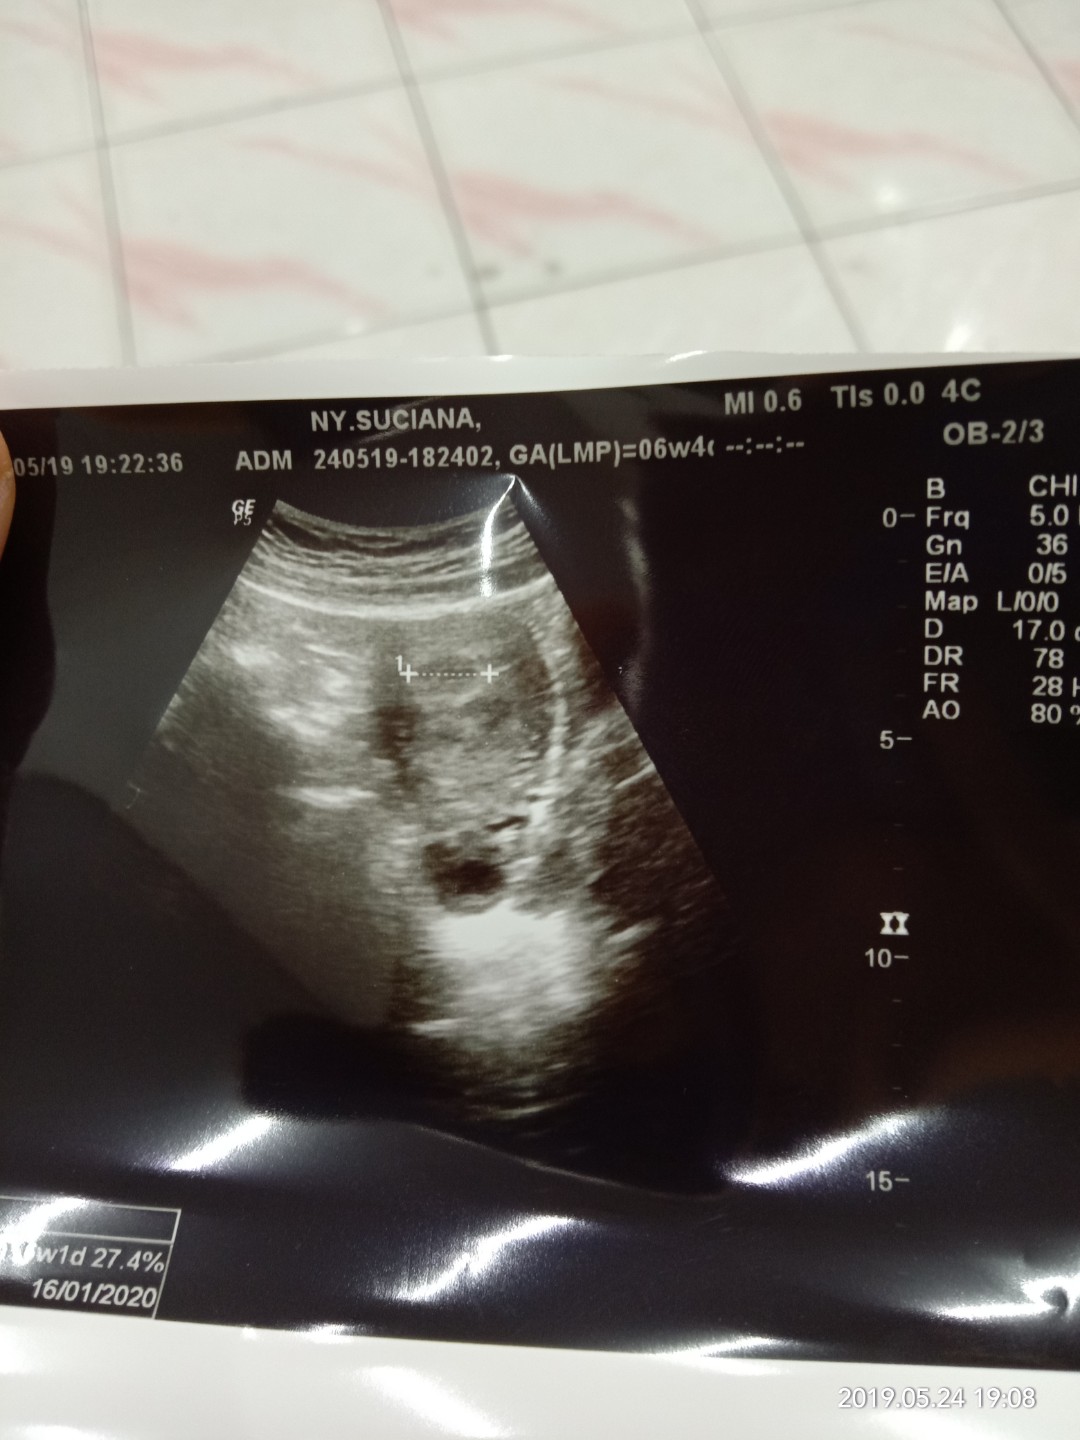

usg

Bun,usia 6w gambar usg nya kygini normal ga sih Bun?? Tadi dokternya bilang, ga berkembang masa?? Disuruh balik lagi seminggu selanjutnya untuk di usg lagi